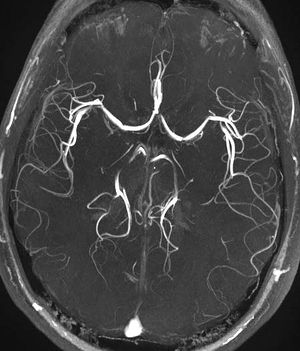

Time-of-flight MRA showing the circle of Willis in the brain. Note the "venetian blinds" artifact visible as the multiple pseudo-stenosis on both the left and right middle cerebral artery

• Time-of-flight (TOF) or Inflow angiography, uses a short echo time and flow compensation to make flowing blood much brighter than stationary tissue. As flowing blood enters the area being imaged it has seen a limited number of excitation pulses so it is not saturated, this gives it a much higher signal than the saturated stationary tissue. As this method is dependent on flowing blood, areas with slow flow (such as large aneurysms) or flow that is in plane of the image may not be well visualized. This is most commonly used in the head and neck and gives detailed high resolution images.

• Venetian blinds: Since the technique acquires images in slabs, non-uniform flip angles due to uneven distribution of the sinc pulses resulting in non-uniform signal intensity